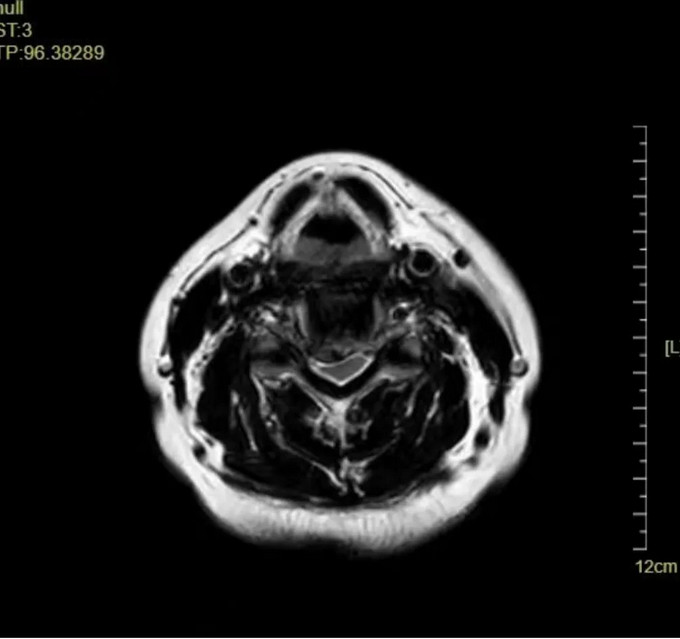

术后影像

颈椎正位DR

颈椎侧位DR

颈椎CT横断位 可以看到突出的骨赘已被切除

颈椎MRI矢状位 颈神经压迫程度明显减轻

术后,吴阿婆颈部手术切口愈合良好,颈部转侧、屈伸时的酸胀疼痛感明显改善,双侧手臂麻木、头晕的症状也消失了,吴阿婆觉得非常神奇,感谢修忠标主任为自己解决了困扰已久的问题。